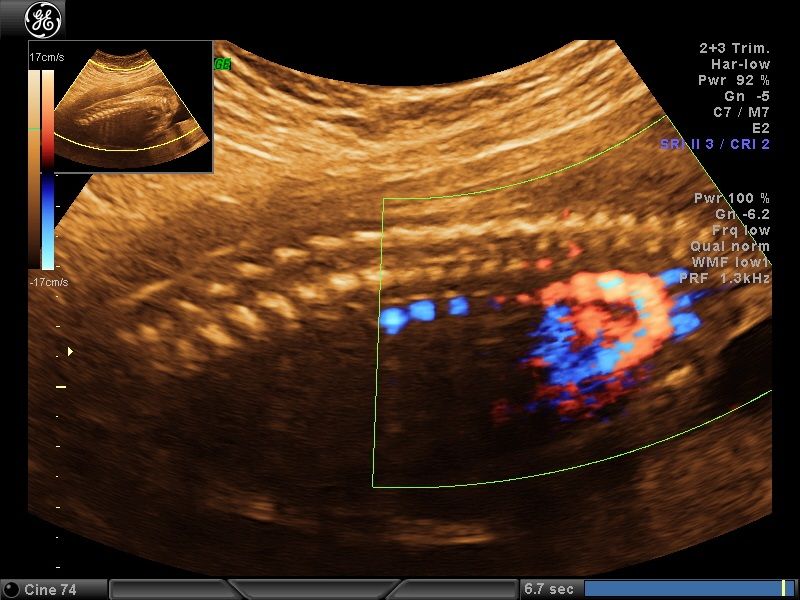

Wykonuję tam około 600 badań „I trymestru ciąży” rocznie, co daje łącznie około 1200 badań z „II trymestrem ciąży” włącznie. Od 15 lat w swoim gabinecie również wykonuję badania prenatalne I, II i III trymestru ciąży w znacznej ilości. To umożliwia mi osiągnięcie doskonałych wyników w diagnostyce tych badań, co stawia mnie w czołówce specjalistów diagnostyki prenatalnej.

Większość swojej kariery zawodowej spędziłem na sali porodowej oraz patologii ciąży. Aktualnie pracuję na sali porodowej. Mam 15-letnie doświadczenie w diagnostyce prenatalnej poparte dużą ilością przebadanych pacjentek i posiadam najszerszy wachlarz certyfikatów z zakresu ultrasonografii płodowej. Corocznie uczestniczę w szkoleniach i kursach ultrasonograficznych.

- diagnostyka prenatalna I,II i III trymestru ciąży z przepływami dopplerowskimi, testem podwójnym (PAPPA i B-HCG), oznaczanie DNA płodowego NIPTY, testy SANCO, NIFTY, VERACITY